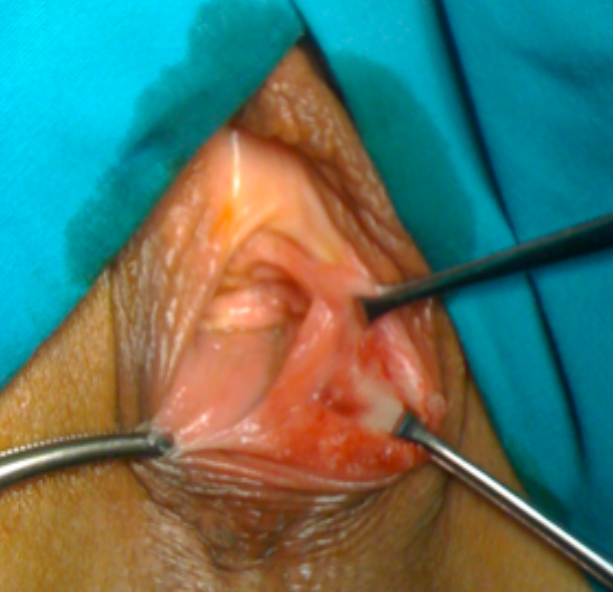

SNAPSHOTS OF IV-DEGREE OASIs REPAIR FOLLOWING INSTRUMENTAL VAGINAL DELIVERY

In this article we report a case of IV-dergee OASIs after instrumental delivery with vacuum cup.